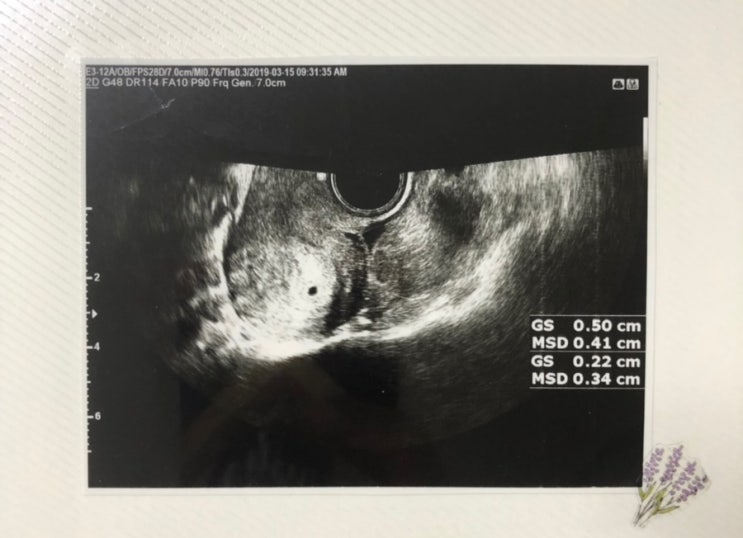

임신 4주, 임신 5주 - 콩알만한 아기집, 난황 확인

결혼 한지 3개월쯤 되던 작년 8월, 생각지도, 계획하지도 않았을 때 자꾸 혈이 비쳐서 산부인과에 갔더니 ...